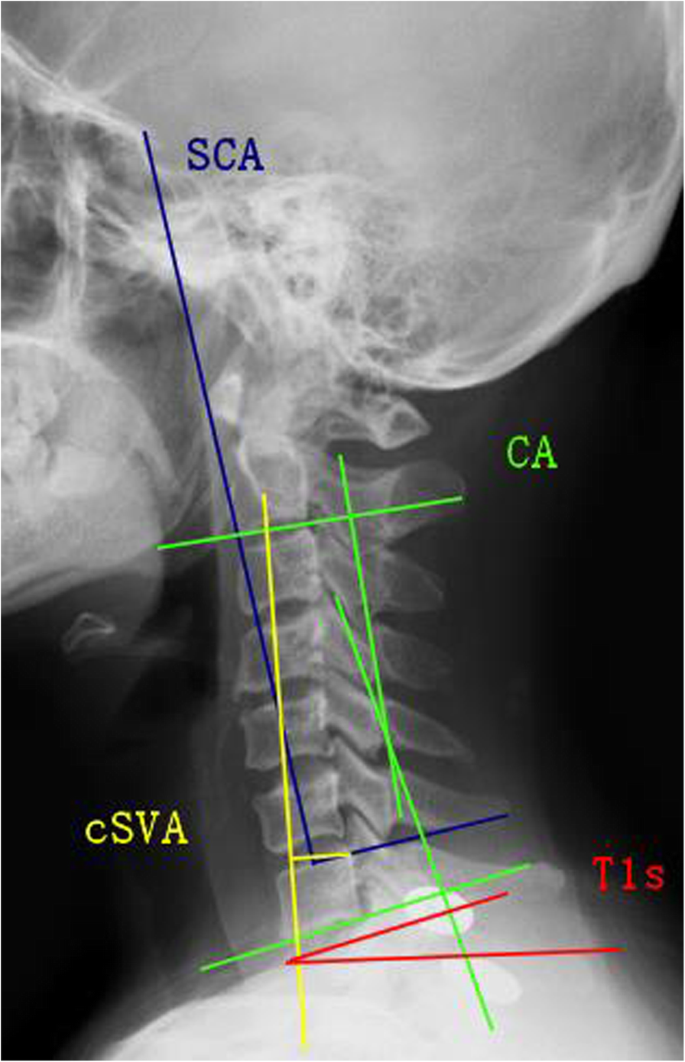

Imaging results were calculated from standard lateral X-rays. All concerning sagittal parameters were evaluated (Fig. 1): (1) spino-cranial angle (SCA), the angle between the C7 slope and the straight line joining the midpoint of the C7 endplate and the midpoint of the sella turcica; (2) T1-slope (T1s), the angle between a horizontal line and the upper endplate of T1; (3) C2-7 lordosis (CA), the angle defined from lower endplate of C2 to lower endplate of C7; (4) C2-7 sagittal vertical axis (cSVA), the distance between the C2 plumb line and the posterior upper endplate of C7; (5) T1s minus CA (T1sCA), the angle of T1-slope minus C2–C7 lordosis; (6) △, the difference values between the preoperative and postoperative or preoperative and follow-up visit for each parameter, such as SCA, T1s, CA, cSVA, and T1sCA.

Spino-cranial angle (SCA), the angle is defined between the C7 slope and the straight line joining the middle of the C7 end plate and the middle of the sella turcica. T1-slope (T1s), angle between a horizontal line and the superior endplate of T1 or C7. C2-C7 lordosis (CA), angle between the lower plate of C2 and the lower plate of C7. C2-C7 SVA (cSVA), the distance from the posterior, superior corner of C7 to the plumbline from the centroid of C2